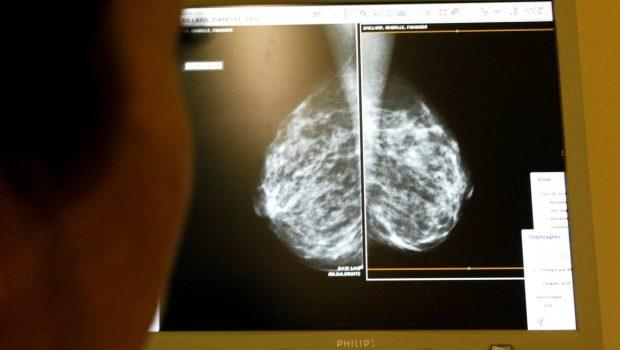

Πυκνός μαστός θεωρείται εκείνος που έχει περισσότερο μαστικό ιστό παρά λιπώδη, κάτι που καθιστά τις μαστογραφίες πιο δύσκολες και αυξάνει τον κίνδυνο ανάπτυξης καρκίνου.

Το πρόβλημα με τον πυκνό ιστό είναι ότι εμφανίζεται λευκός στις κλασικές μαστογραφίες, όπως και οι όγκοι, γεγονός που δυσκολεύει τον εντοπισμό τους.

Η ακτινολόγος δρ Νερίς Φόρεστερ, σύμβουλος σε νοσοκομεία του Newcastle, εξηγεί ότι περίπου το 40% των γυναικών έχουν πυκνό μαστικό ιστό, κάτι που γίνεται γνωστό μόνο όταν υποβληθούν σε μαστογραφία. «Ο πυκνός ιστός δεν είναι από μόνος του ανησυχητικός, αλλά συνδέεται με ελαφρώς αυξημένο κίνδυνο για καρκίνο του μαστού», είπε.

«Όταν το στήθος είναι πολύ πυκνό, είναι σαν να προσπαθείς να βρεις ένα λευκό σύννεφο μέσα σε έναν συννεφιασμένο ουρανό», είπε χαρακτηριστικά περιγράφοντας τη δυσκολία εντοπισμού καρκίνου.